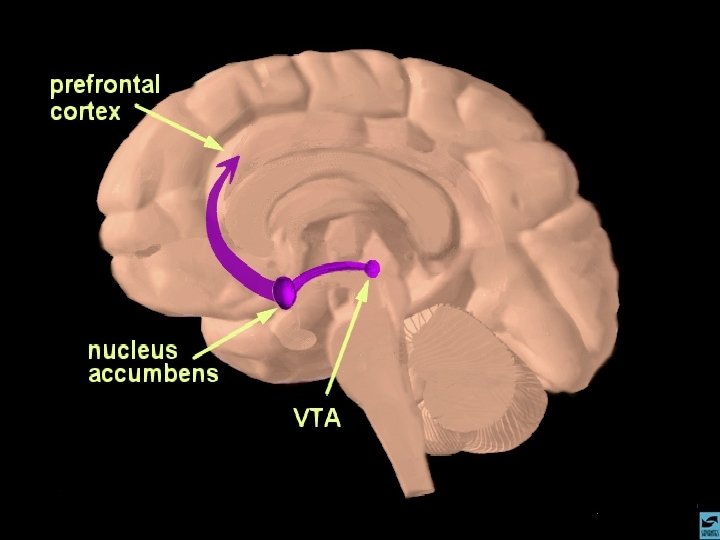

ANFETAMINAS E COCAÍNA EFEITOS CEREBRAIS: ATIVA OS SISTEMAS DOPAMINÉRGOS MESOLÍMBICOS E MESOCORTICAIS, INIBINDO A RECAPTAÇÃO DE DOPAMINA NOS TERMINAIS SINÁPTICOS E PROMOVENDO SUA LIBERAÇÃO NAS SINAPSES.